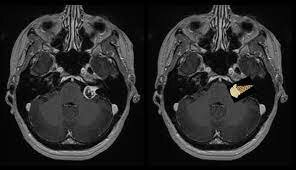

El doctor Raymond Damadian demostró que la resonancia magnética podía ser usada para detectar enfermedades porque distintos tipos de tejidos emiten señales que varían en su duración, en respuesta al campo magnético.

Damadian creó la primer equipo de resonancia magnética en 1972. Pocos meses más tarde aplicó a una patente para para su invento con el título “Aparato y método para detectar tejidos cancerígenos”. La patente fue otorgada el 1974 en Estados Unidos, y fue la primera que se dio en el campo de la resonancia magnética.

Reconociendo la importancia del descubrimiento de Damadian, el investigador Paul Lauterbur desarrolló la técnica para generar las primeras imágenes en resonancia magnética en 2 y 3 dimensiones utilizando gradientes, y publicó la primera en 1973.

Mansfield y Lauterbur recibieron en 2003 el premio Nobel de Medicina por sus descubrimientos en el campo de las imágenes de resonancia magnética.